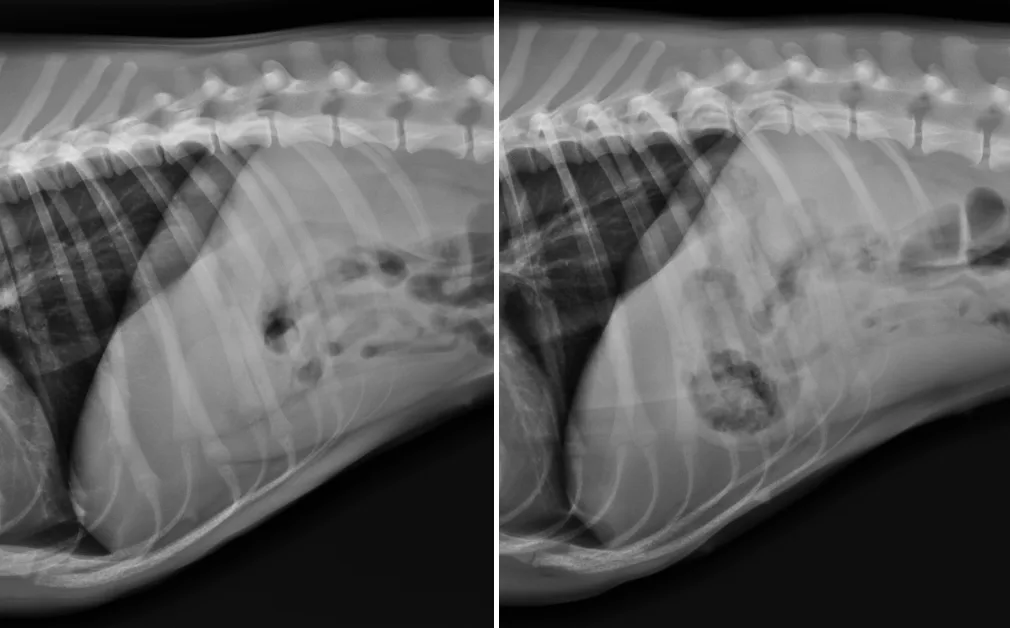

Objects appeared differently in each media. All objects except a food storage bag were identifiable when radiographed in air, and many became obscured in water. Some objects appeared predominately opaque in air and relatively lucent in water or vice versa. Intermediate transparency could be interpreted radiographically as fat. Repositioning a patient may alter the environment surrounding the foreign body, causing a markedly different appearance on one radiographic projection versus another.